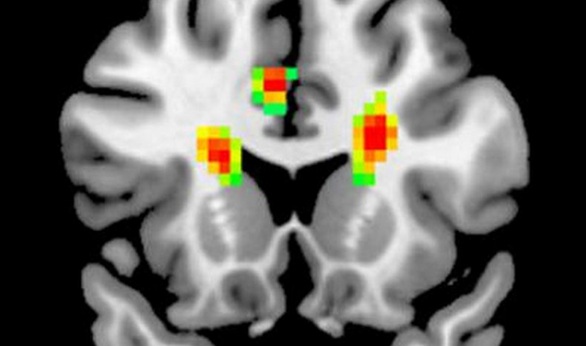

كشفت دراسة صينية أن الشعور بالحب يجعل العقل أكثر مرحا، حيث يتم إحاطة 12 جزءا من المخ بالأشياء الايجابية عند شعور الشخص بالمشاعر الرومانسية.

وذكرت صحيفة الاندبنديت البريطانية أنه من خلال تجربة أجريت علي 100 شخص، تبين عن طريق التصوير بالرنين المغناطيسي الوظيفي أن الحب يتسبب في تدفق الدم إلي المخ.

وأوضح تقرير الاندبندنت، أن نتائج تلك الدراسة سلطت الضوء علي أهمية الآليات العصبية الناتجة من الحب الرومانسي من خلال التحقيق نشاط للمخ.